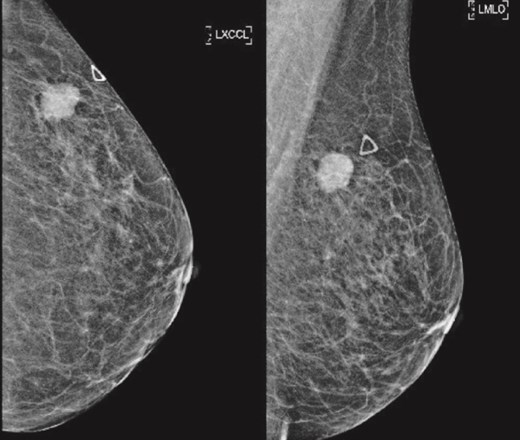

(Left) Mammography cranial-caudal view of left breast; (Right) Mammography mediolateral oblique view of the left breast: Left upper outer breast spiculated mass with minimal architectural distortion.